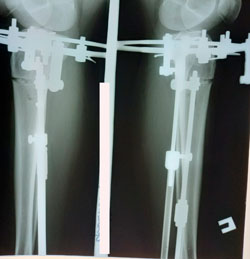

перед фиксацией

Вложения